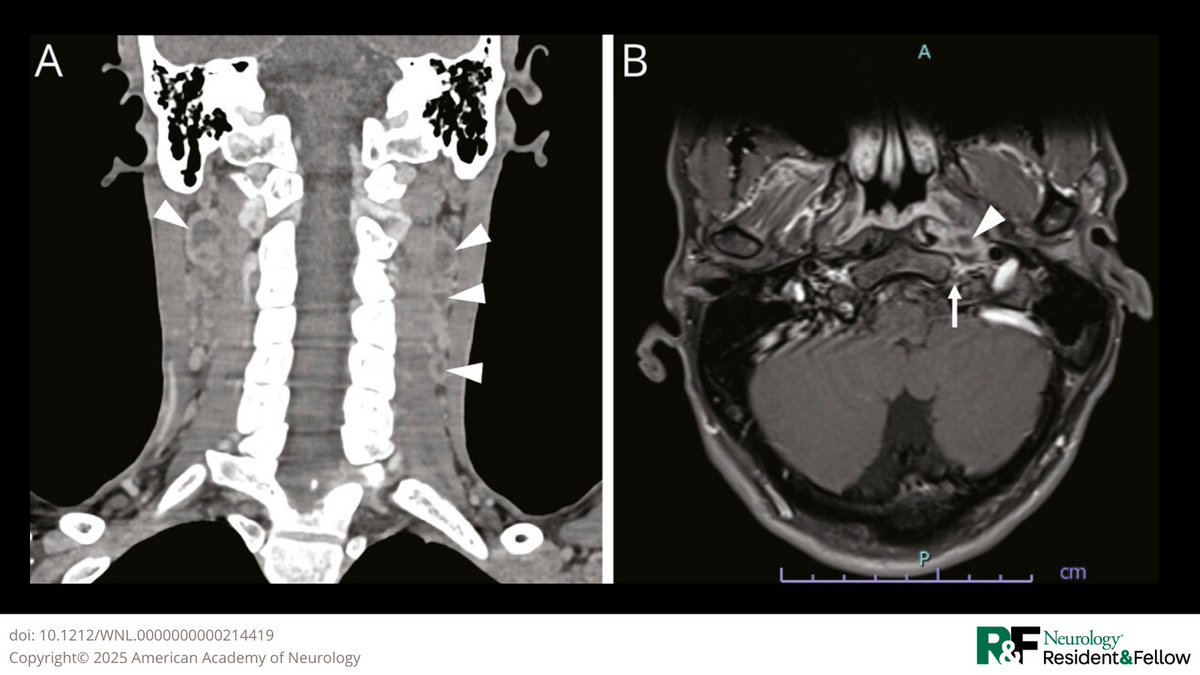

Teaching NeuroImage: Isolated Hypoglossal Nerve Palsy: From Tuberculous Abscess https://t.co/K1N0nK0eKn